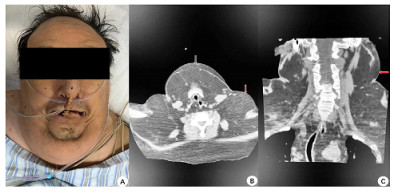

入院查体:患者呈昏迷状,双侧瞳孔等大等圆,直径3 mm,对光反射迟钝,颈部(图 1)和肩部(图 2)分别可见7 cm×4 cm及5 cm×6 cm大小软组织肿胀,质软,腹部及双侧大腿内侧(图 3)可见5 cm×6 cm软组织肿胀,质软,双肺呼吸音粗,双肺可闻及少许湿啰音,心律齐,各瓣膜听诊区未闻及病理性杂音,腹部膨隆,腹部查体不配合。入院后相关检查见表 1,腹部超声提示脂肪肝,心脏超声示左室壁运动弥漫性减低、左室壁肥厚,左室射血分数47%。

| A:患者下颌及颈部脂肪隆起;B:颈部CT平扫(轴位-下颌及颈部皮下脂肪影增多);C:颈部CT平扫(冠状位-颈部皮下脂肪影增多) 图 1 患者下颌及颈部病变(红色箭头所示) |

入院后给予呼吸机辅助通气,美罗培南抗感染、维生素B1肌注、营养支持等治疗,患者神志逐渐恢复,可自主睁眼,但不能按指令动作,呼吸机条件逐渐下调,并于2月4日成功脱机拔管。复查相关实验室检查见表 2,行头颅CT示脑室系统扩大,脑沟、脑裂稍宽,脱髓鞘改变;颈部CT示颈部大量脂肪沉积(图 1、图 2);胸部CT示双肺散在斑片影,考虑感染;腹部CT示腹腔及皮下脂肪影增多(图 3)。结合患者既往长期大量饮酒史、查体及影像学表现,考虑诊断:马德龙病、Wernicke脑病。患者不能配合指令动作,未行头颅磁共振检查。